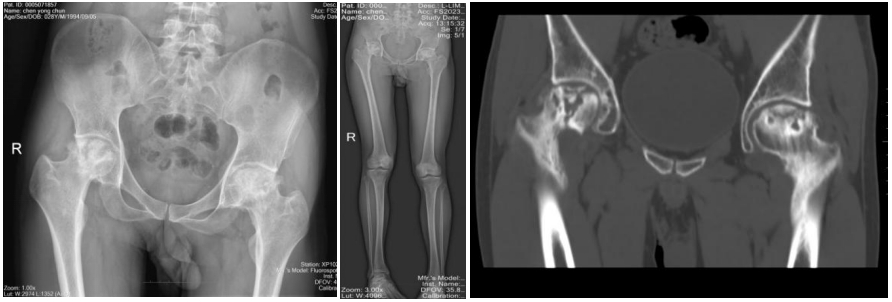

刚入院时,患者在进行主动活动时,双侧髋关节疼痛剧烈,感到十分痛苦。查体可见其双下肢不等长,右下肢较左下肢短缩约3cm,双侧髋关节被动活动时可感受到明显的抵抗。袁勇专家团队接诊后,立即完善了X线、CT及核磁等检查,发现患者双侧股骨头已缺血性坏死,并且因常年的磨损已导致双侧髋关节骨性关节炎的发生,股骨头骨质增生、硬化,致双侧髋关节僵硬

患者术后复查双侧髋关节假体位置良好,双下肢已恢复到同一长度,得以重新自由地行走。此次手术的顺利完成,充分体现了急诊医学部急诊外科医护团队积极探索,勇于创新的进取精神,更展示了对待患者病痛时的细心、耐心和专业的诊疗水平。今后,急诊医学部急诊外科将不断探索和学习,优化诊疗流程,为人民群众的生命健康、生存质量继续保驾护航。